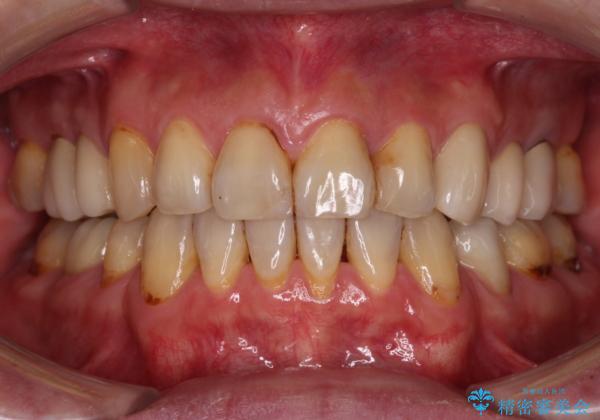

- むし歯による奥歯の痛みを気にして来院された患者様です。

神経にまでむし歯の及んでいる歯や、既に根管治療がされている歯に痛みがあったため、まずは根管治療を行うこととしました。

その後、以前行った抜歯矯正の後戻りをインビザライン・ライトにより改善し、むし歯や銀歯はオールセラミッククラウンにて補綴治療することとしました。

痛みは速やかに引き、銀歯や黒く変色したむし歯がセラミッククラウンで自然な色合いに仕上がり、患者様には大変満足していただきました。